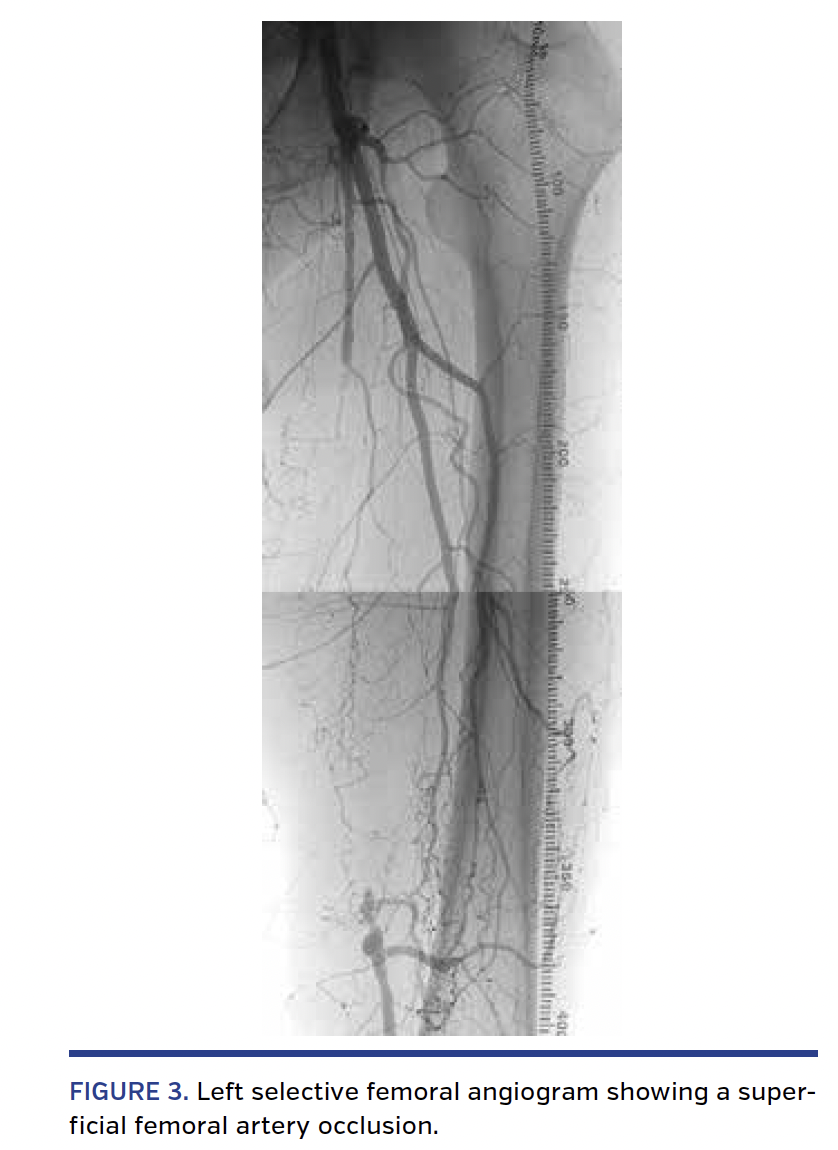

Procedure description. First, from a retrograde right femoral access, standard diagnostic angiograms were obtained, and a 6 Fr, 45 cm contralateral sheath was advanced to the level of the left common femoral artery. A selective angiogram showed a 20 cm-long SFA occlusion with a widely patent popliteal artery and 2-vessel run-off (Figure 3). A “tap” test was performed with a 0.018˝ Bentson wire (Boston Scientific) backed with a 5 Fr angled catheter with the distal tip placed in the proximal SFA just above the proximal cap of the CTO. This confirmed a fibrous “hard” CTO. The catheter and wire were then exchanged for a 4 x 100 mm Sterling balloon (Boston Scientific) advanced at the site of the CTO. The ShockWire was introduced into the balloon catheter. A second unsuccessful tap test was performed with the inactivated ShockWire. After activation of the ShockWire, the proximal cap and the first 2 cm of the occlusion were easily crossed. The inactivated ShockWire was then advanced through several centimeters of the occlusion. In the middle third of the 20 cm-long CTO, three areas of resistance were encountered despite repeated attempts to cross with the inactivated ShockWire. All three areas were readily crossed within 10 seconds of ShockWire activation. After crossing the entire length of the CTO, an angiogram was performed showing the tip of the ShockWire in the subintimal space adjacent to the distal cap. After removing the ShockWire, the wire was reinserted into the balloon catheter with a short bend at its distal tip (~2 mm, 45°). The ShockWire was then oriented toward the true lumen, and after activation, reentry was readily achieved (Figure 4). The balloon catheter was then advanced distal to the CTO, and the ShockWire was exchanged for a workhorse 0.018˝ wire. After predilation, the CTO was treated with 5 mm-long drug-coated balloons according to standard technique with an excellent angiographic result and no complications (Figure 5).